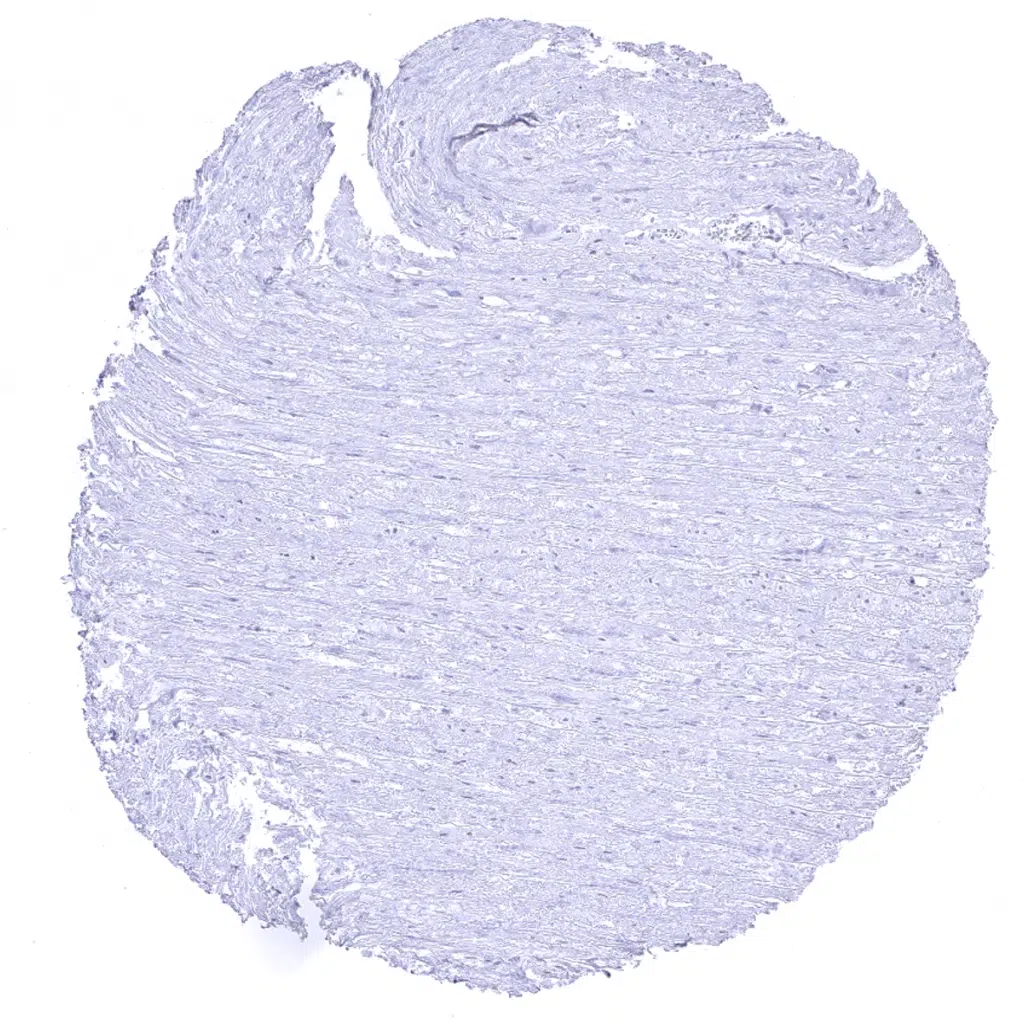

Aorta, media